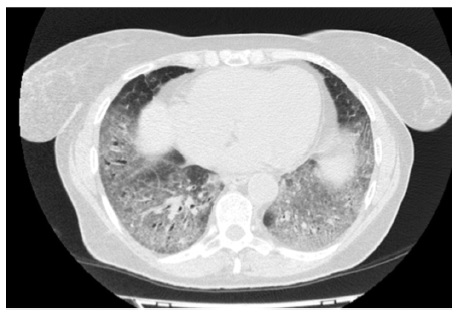

КТ ретроперитонеального фиброза: Изображения и диагностика